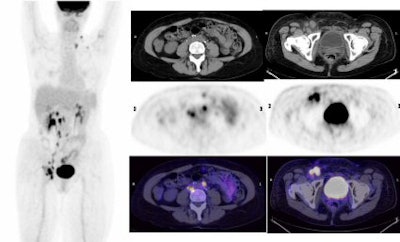

| Above and below, a 55-year-old woman with cervical carcinoma. Lymph node metastases are seen on the transaxial PET, CT, and fused PET/CT images. All images courtesy of Stanford University. |